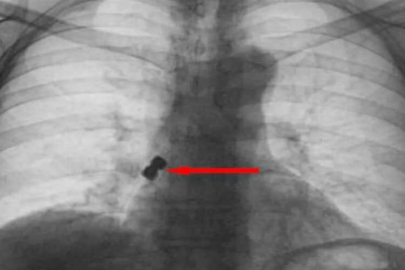

İmplant vidası soluk borusuna kaçtı az daha canından oluyordu! Haber

İmplant vidası soluk borusuna kaçtı az daha canından oluyordu!

Van'ın İpekyolu ilçesinde ikamet eden F.T. isimli hasta, dış merkezli bir diş kliniğinde implant tedavisi gördüğü sırada, implant vidası yanlışlıkla soluk borusuna kaçtı. Nefes borusuna kaçan vida nedeniyle hasta, ileri tetkik ve tedavi amacıyla Van Eğitim ve Araştırma Hastanesi'ne sevk edildi. Göğüs Cerrahisi uzmanları Dr. Sadullah Aksoy ve Dr. Beniz İrem Ersoy Şığva tarafından hastaya bronkoskopi işlemi uygulandı. Sol akciğerin üst lobunda saplanmış şekilde tespit edilen vida, vidalı yapısı ve bulunduğu konum nedeniyle güçlükle yerinden oynatılabildi. Yapılan uzun ve titiz müdahale sonrası vida yerinden çıkarılamasa da hasta bir süre sonra geçirdiği öksürükle birlikte implant vidasını midesine gönderdi. Vida, daha sonra doğal yollarla vücuttan atıldı. "İmplant tamamen çıkarılamadı ancak yerinden oynatılabildi" Konuya ilişkin konuşan Göğüs Cerrahi Op. Dr. Sadullah Aksoy, bir diş merkezinde diş tedavisi sırasında hastanın çenesine yerleştirilen implantın vida kısmının işlem esnasında yanlışlıkla aspire edildiğini belirtti. İlk olarak hastanenin ek hizmet binasında çekilen tomografi sonucunda, vidanın sol akciğerin hava yollarının yaklaşık dördüncü dalına kadar ilerlediği tespit edildiğini ifade eden Op. Dr. Aksoy, "Geçtiğimiz cumartesi günü öğle saatlerinde tarafımıza ulaşıldığında, hastanın Van Eğitim ve Araştırma Hastanesi'ne yönlendirilmesini istedik. Burada acil bronkoskopi planı yapılarak hasta kabul edildi. Hasta geldiğinde genel durumu iyiydi; solunumunu tamamen engelleyen bir bronş tıkanıklığı söz konusu değildi. Aynı gün hastamızı hazırladık. Bronkoskopi sırasında, implant vidasının sol üst lobun anterior segment bronşuna saplanmış pozisyonda olduğunu gördük. Üroloji bölümünde taş çıkarma işlemlerinde kullanılan cihazla müdahale ettik. İlk denemede implant tamamen çıkarılamadı ancak yerinden oynatılabildi. Bunun üzerine bir süre bekleyip hastayı yeniden bronkoskopi için hazırlamaya başladık. İşlem yaklaşık 3,5-4 saat sürdü ve saat 18.30 civarında hasta işlemden çıkarıldı" dedi. "İmplant vidası öksürük sonrası akciğerden çıktı" Daha sonra hasta için yeniden bronkoskopi planladıklarını ancak bu süreçte hasta şiddetli bir öksürük geçirdiğini anlatan Aksoy, "Şiddetli öksürük sonrası yapılan kontrol akciğer filminde implant vidası görünmedi. Bunun üzerine toraks ve batın BT (bilgisayarlı tomografi) görüntülemesi istedik. Sonuçlarda implantın akciğerden çıktığı ve vücutta herhangi bir yerde bulunmadığı tespit edildi" diye konuştu. "İyileşme süreci sorunsuz tamamlandı" Göğüs Cerrahi Op. Dr. Beniz İrem Ersoy Şığva ise merkezde ilk kez böylesi bir vakayla karşılaştıklarını ifade ederek, "Vidanın dişe özel ve vidalı yapıda olması, ayrıca bronşların küçük dallarına saplanması nedeniyle çıkarma işlemi beklenenden uzun sürdü. Ancak hasta takiplerinde herhangi bir komplikasyona rastlanmadı ve iyileşme süreci sorunsuz tamamlandı" şeklinde konuştu.